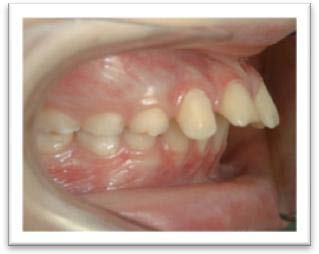

Inversé articulé précoce

Inversé unilatéral à droite